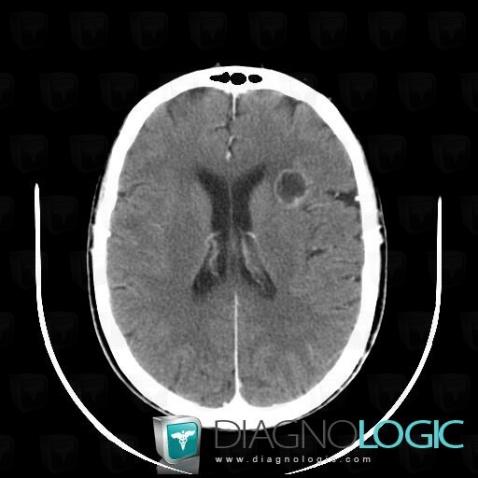

Metastasis, Cerebral hemispheres, CT

Here is the specific information in the key image above:

- Diagnosis Metastasis, Location(s) Cerebral hemispheres, with gamuts Intracerebral lesion with moderate enhancement